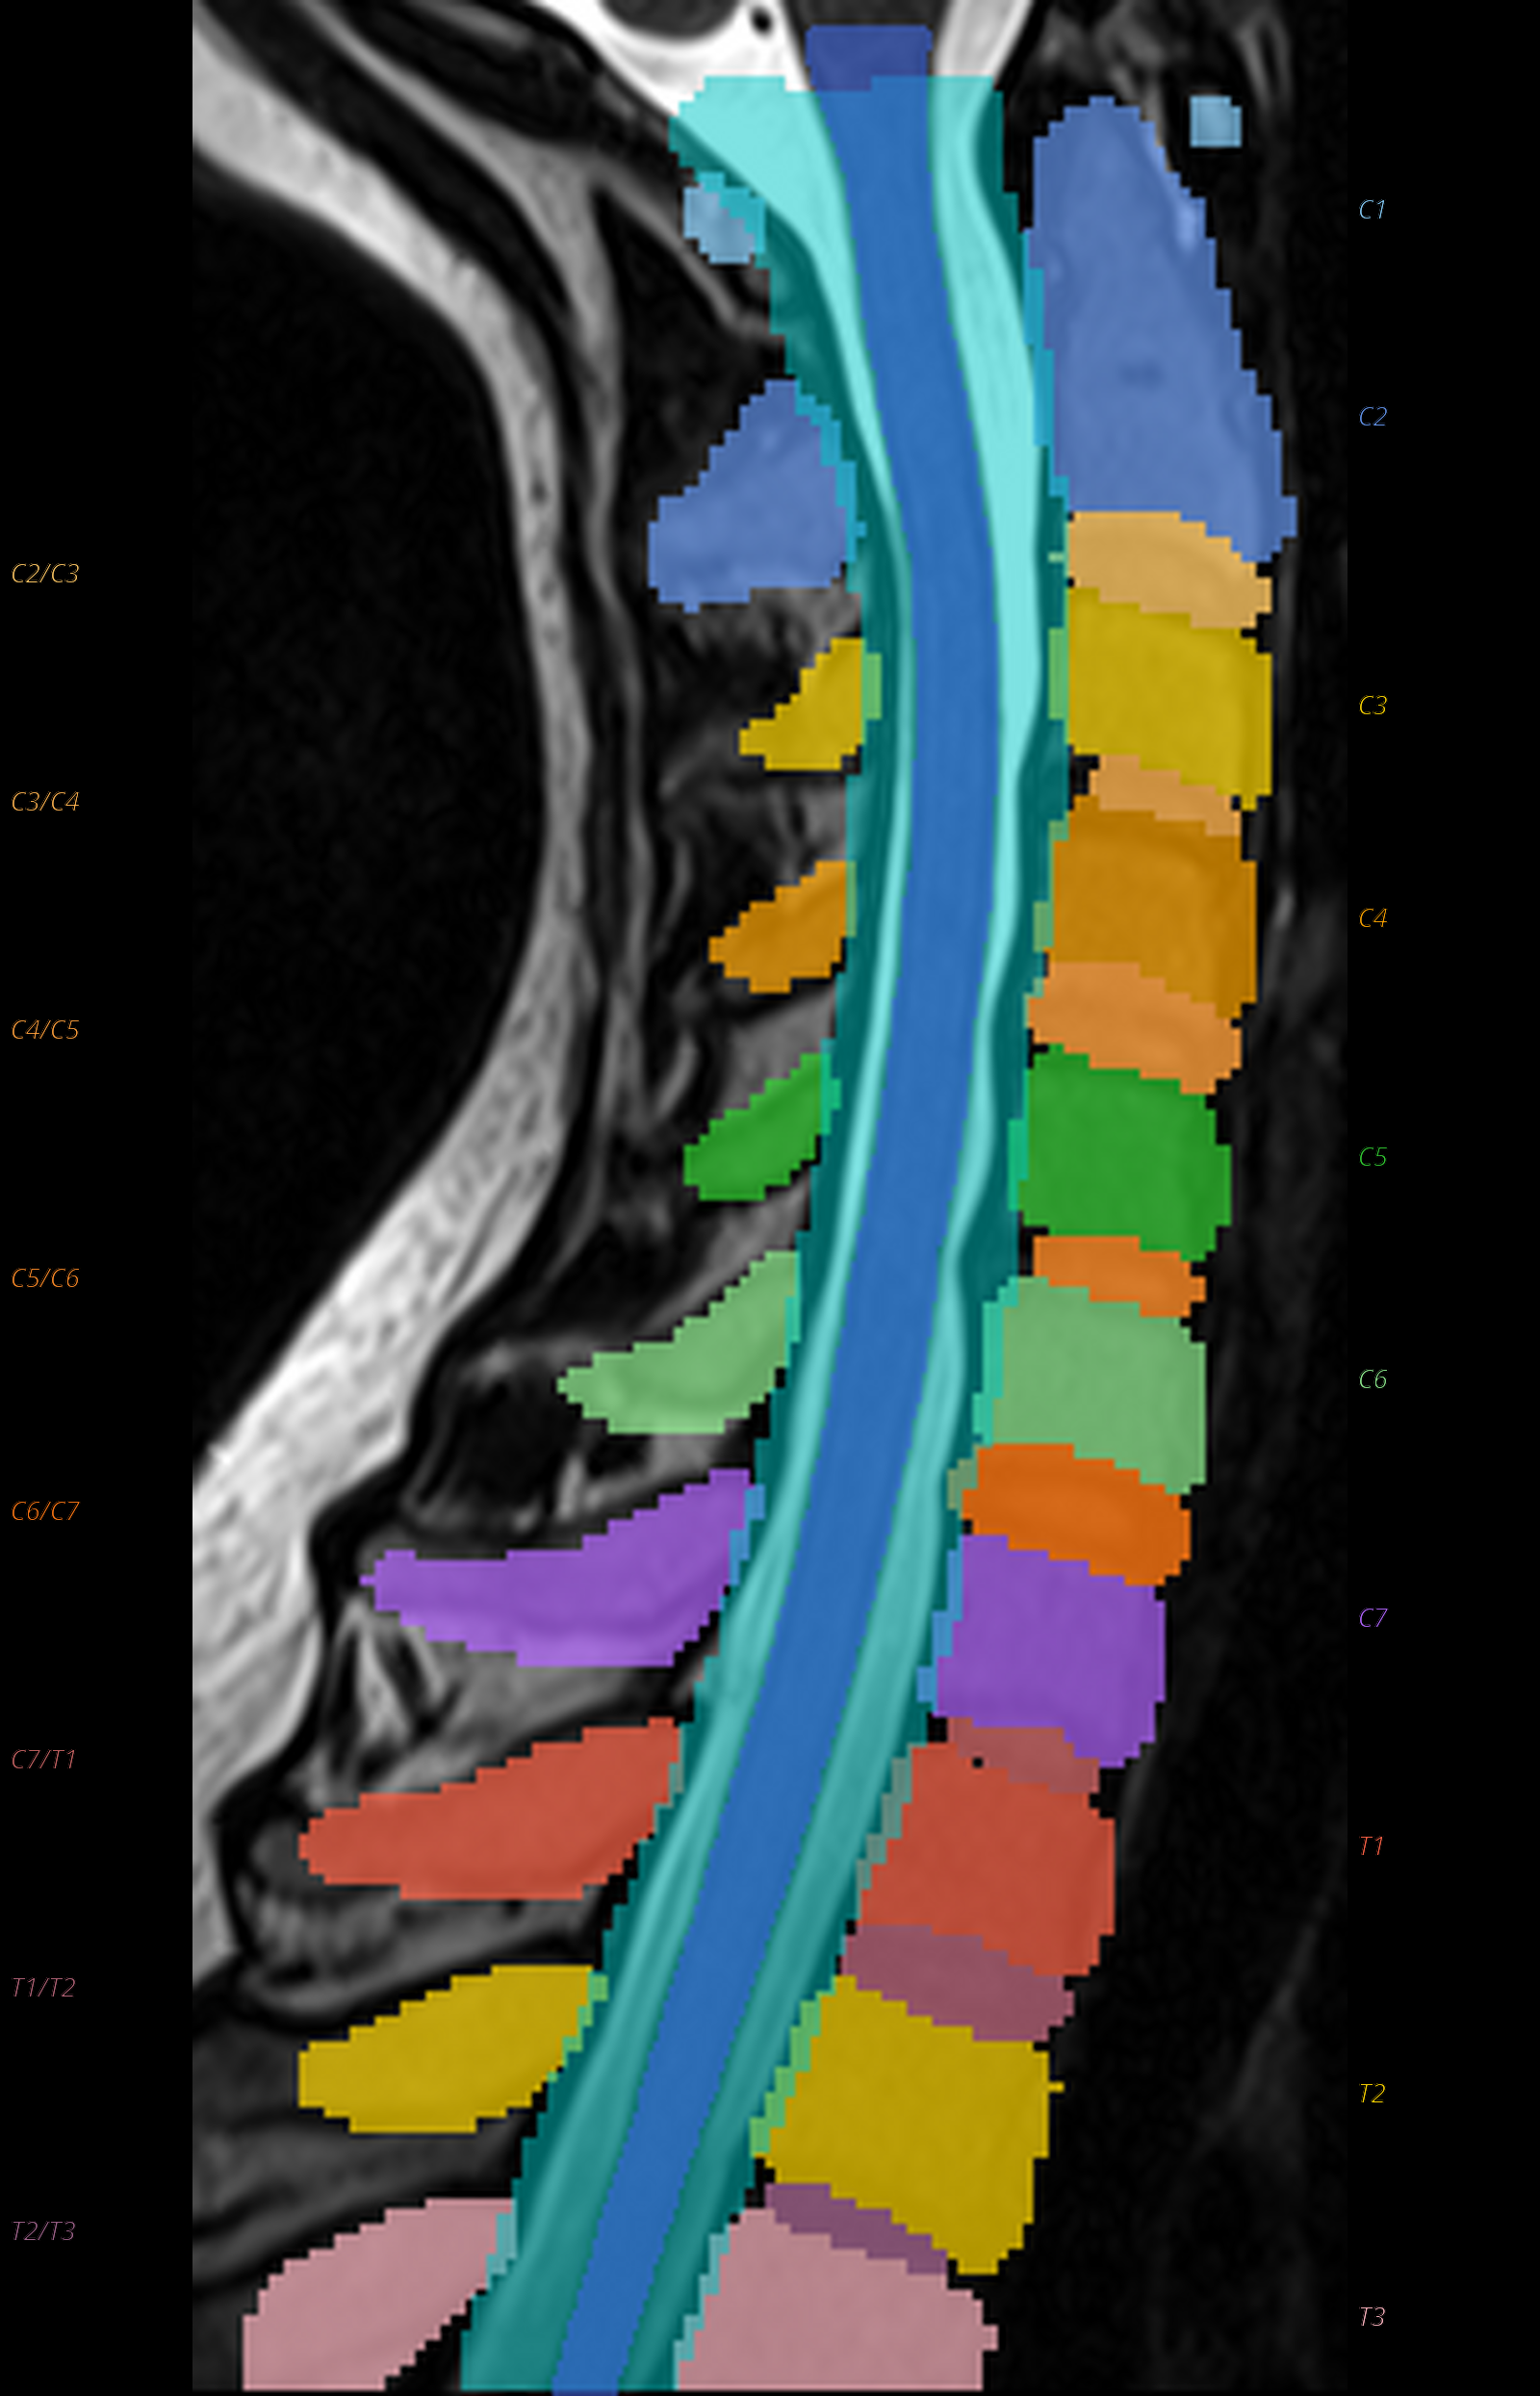

QC: TotalSpineSeg Montage

Sagittal view showing colored vertebrae, discs, cord (blue), canal (cyan), with anatomical labels.

What to look for:

- ✅ Vertebrae are correctly ordered (no label jumps)

- ✅ Disc labels correspond to adjacent vertebrae

- ❌ FAIL: Missing vertebrae or shifted labels